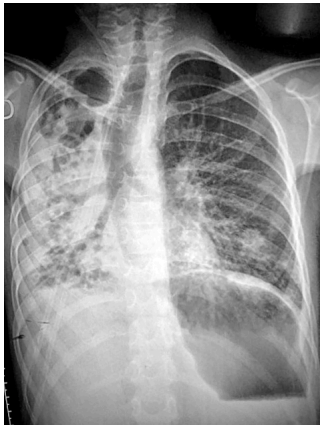

Masculino de 10 años, refirió 1 año de evolución con tos persistente, múltiples tratamientos, últimos 10 días con dolor en hipocondrio izquierdo, tos productiva en accesos largos, incontables golpes, dificultad respiratoria, cianosis peribucal, fiebre de 39ºC. Exploración física peso 19 kg (-3.2 DE), talla 123 cm (-2.6 DE), frecuencia cardiaca 130 lpm, frecuenciaturas mediastinales hacia la derecha, hiperinsuflación compensatoria contralateral y diámetro traqueal incrementado (Figura 1). TAC torácico con datos de neumonía lobar, bronquiectasias, neumatoceles derechas, diseminación broncógena izquierda, adenomegalias paratraqueales derechas. Diámetro traqueal anterior:

En el caso presentado, tenemos un paciente con antecedentes en donde se reporta historial recurrente de afectación en las vías respiratorias, sino que además afectación en el tubo digestivo, más específico en esófago, por ello el realizar una radiografía de tórax permitió tener más claridad para el diagnóstico, en esta se reportó un infiltrado grueso con predominio en laguna pulmonar derecha, además de una clara dilatación en las estructuras correspondientes a la vía aérea media y baja; esto motivo se solicitaran exámenes más específicos, que permitieron, la medición más precisa, de las estructuras anatómicas.

Figura 1: Radiografía con desviación de estructuras mediastinales hacia la derecha incluyendo tráquea, corazón y mediastiano, hemitórax con